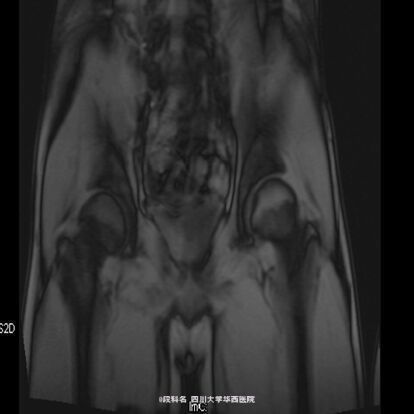

查体:右髋局部无红肿,有压痛,皮温不高,感觉无减退。右侧髋伸屈、外展、内收,因疼痛无法评测。右膝屈曲4级,伸膝3级,踝背伸、跖屈4级 。左侧肌力正常,肌张力正常。右侧直腿抬高试验40°(+),加强实验(+),右侧4字实验(+)。辅助检查:当地医院CT检查示:L4/5椎间盘轻度膨出,L5/S1椎间盘轻度突出,建议MRI检查。我院血常规示:血小板计数 425 10X9/L,白细胞计数 12.26 10^9/L,中性分叶核粒细胞绝对值 8.34 10^9/L。生化示:血沉53.mm/h,C反应蛋白(CRP)42.80mg/L。痰涂片抗酸染色(连续3次):未查见抗酸杆菌。免疫球蛋白A 4050.00 mg/L ↑ 免疫球蛋白M 2240.00 mg/L ↑C-反应蛋白 31.80 mg/L ↑。T细胞亚群正常。CD3细胞亚群 71.40 %CD4细胞亚群 37.00 % CD8细胞亚群 29.80 % CD4/CD8比值 1.24。痰培养示:产酸克雷伯氏菌 混丛,较多。结核抗体检测 阴性 。骨盆MRI示:右侧骶髂关节面骨质见斑片状长T2WI及长T1WI信号,关节间隙模糊、局部狭窄,邻近髂腰肌、梨状肌、臀肌群见斑片状T2WI高信号影。左侧骶髂关节及双侧髋关节未见确切异常。